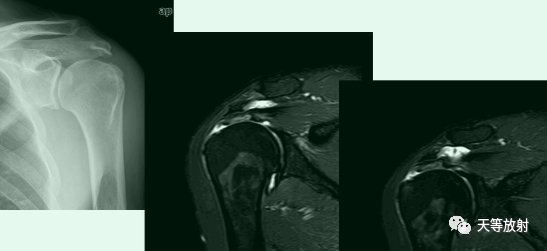

骨性Bankart病变

-

MR间接关节造影1.5T轴位T1W脂肪抑制(TR=460s,TE=90s)

SLAP、Bankart合并Hill-Sach损伤

Hill-Sachs损伤

Hill-Sachs损伤:肩关节前脱位时,肱骨头撞向关节盂缘可导致肱骨头的后外侧的嵌插骨折

MR间接关节造影1.5T轴位T1W脂肪抑制

MR间接关节造影1.5T冠状面T1W脂肪抑制

Hill-sachs,Bankart,关节囊损伤